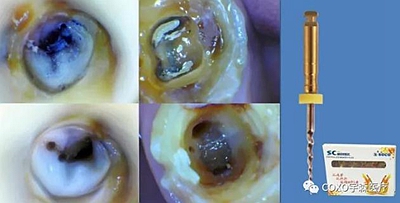

6,根管器械折斷

1.嚴(yán)格控制器械在根管內(nèi)的使用次數(shù)

2.充分了解根管系統(tǒng),在狹窄處切勿強(qiáng)行通過

3.對(duì)復(fù)雜的根管:如分叉或融合的根管、急彎的根管、S形根管,鈣化根管使用新的鎳鈦器械預(yù)備,充分潤(rùn)滑、沖洗、多提拉、使用專用銼,必要時(shí)結(jié)合手?jǐn)U銼完成根管預(yù)備

4.不能用力過猛,在感到阻力時(shí)應(yīng)用輕微的力“啄”的手法運(yùn)動(dòng),每次前進(jìn)1mm,直到到達(dá)工作長(zhǎng)度。

6.常規(guī)使用EDTA

7.次氯酸鈉液沖洗

8.每次使用擴(kuò)銼前,仔細(xì)檢查器械的表面, 一旦發(fā)現(xiàn)有缺陷立即棄用。